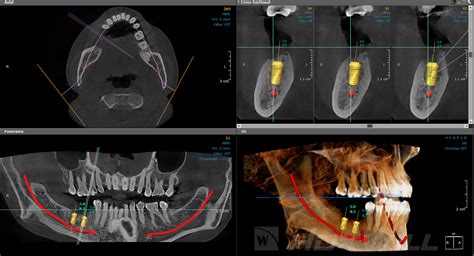

Ejemplo de imagen obtenida mediante TAC Dental

Fases del Tratamiento con Implantes y el Rol del CBCT

La CBCT juega un papel importante en las diferentes fases del tratamiento con implantes:

- Fase Pre-quirúrgica: Corresponde a la fase previa a la colocación de los implantes. Esta fase se compone de dos etapas: etapa de diagnóstico por imagen pre-quirúrgica y etapa de planificación pre-quirúrgica. En la etapa de diagnóstico por imagen pre-quirúrgica se analiza la situación inicial del paciente, evaluando no sólo el sitio a rehabilitar sino también el estado general de la dentición remanente cuando ésta exista.

- Fase Quirúrgica: Esta fase se centra fundamentalmente en el tratamiento quirúrgico, en el que la imagenología juega un rol importante para que el clínico asegure la correcta posición y orientación del implante durante e inmediatamente después de la cirugía.

- Fase de Mantenimiento: Corresponde al período comprendido desde la colocación del implante, prolongándose por todo el tiempo que este implante permanezca en el tejido óseo. Lo que se busca en esta fase a través del examen imagenológico es determinar posibles cambios de posición del implante.